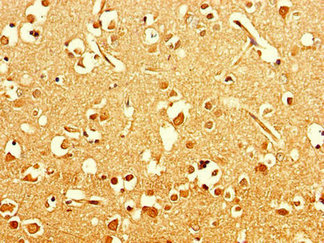

Immunohistochemistry of paraffin-embedded human brain tissue using CSB-PA836246LA01HU at dilution of 1:100